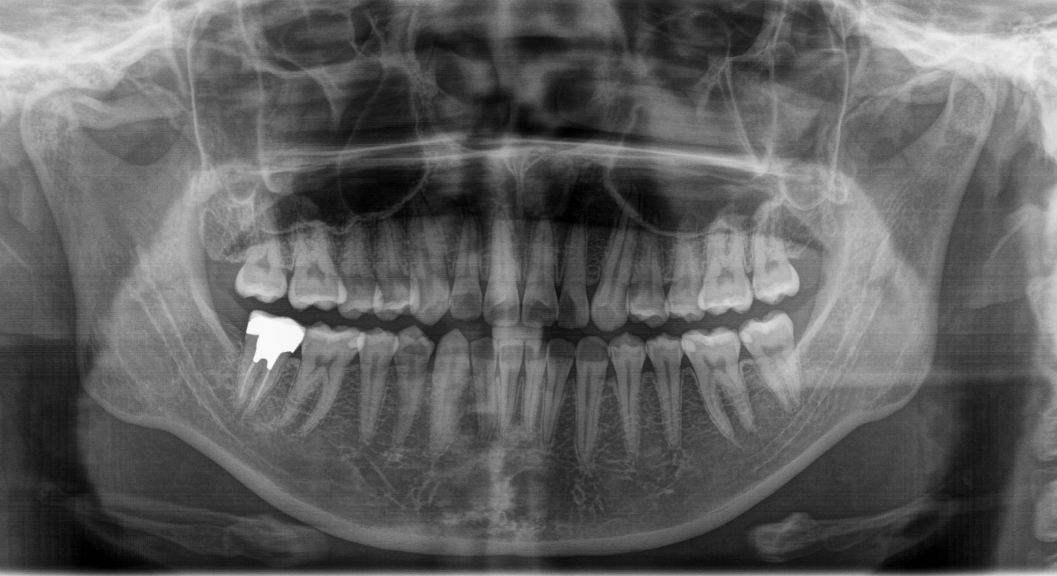

パノラマX線撮影機・CT撮影機

パノラマX線撮影機 CT撮影機

従来型のレントゲンより放射線量が10分の1のデジタルレントゲンを採用しています。

歯のレントゲン写真の放射線量は、日常生活で自然界から受ける量のわずか1~2日程度でしかありませんので、安心してレントゲン撮影を受けることができます。また撮影後に現像する必要がないため、撮影後すぐに確認する事が可能です。

CT撮影は、歯の根の長さ、根管の数、湾曲度合い、根尖部の骨の透過像、歯槽骨の高さなどを確認します。根管治療、歯周組織再生療法、インプラントなどの高度な治療には欠かせない機械になります。